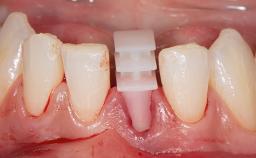

Surgical Management of Peri-Implantitis: Open-Flap Debridement with Seven-Year Follow-up After Treatment

This case describes both a surgical and an anti-infective approach for the management of peri-implantitis, including treatment of the entire dentition to eliminate any deep periodontal pockets that could serve as reservoirs for bacterial re-colonization at the implant site. A 65-year-old female patient was referred to the periodontist in 2013 for assessment and management of an infection at implant 12. On examination, probing depths at implant 12 were 11 mm with suppuration and bleeding on probing.